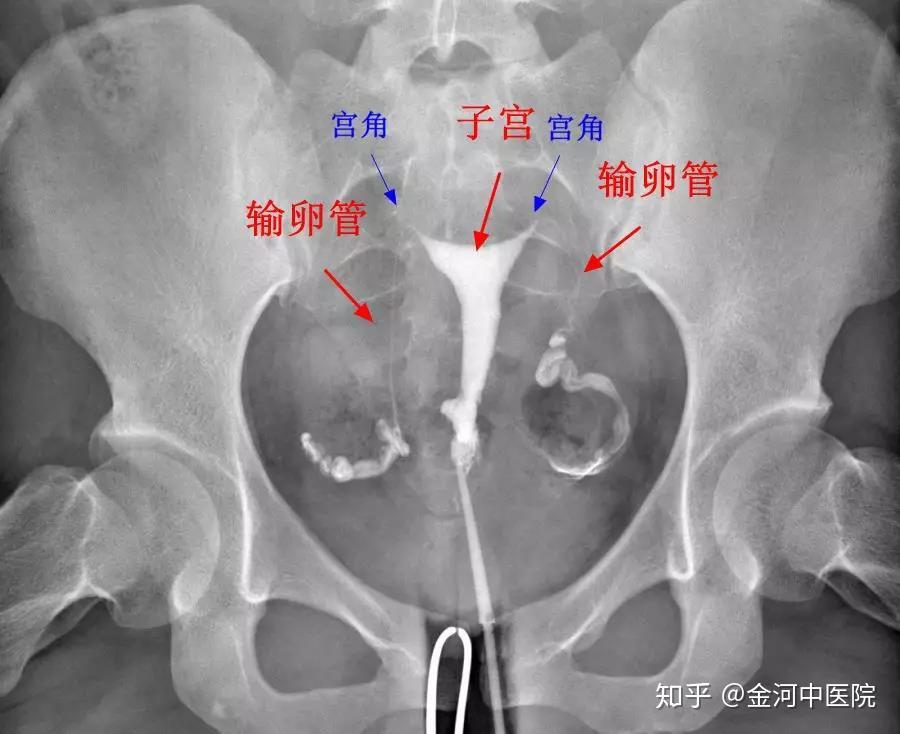

国际上规定,x线下子宫输卵管造影检查才是诊断输卵管的金标准.

1,输卵管造影检查:输卵管造影经x线的子宫输卵管造影是通过导管瞎宫

子宫输卵管造影术ppt

子宫输卵管造影检查的临床应用